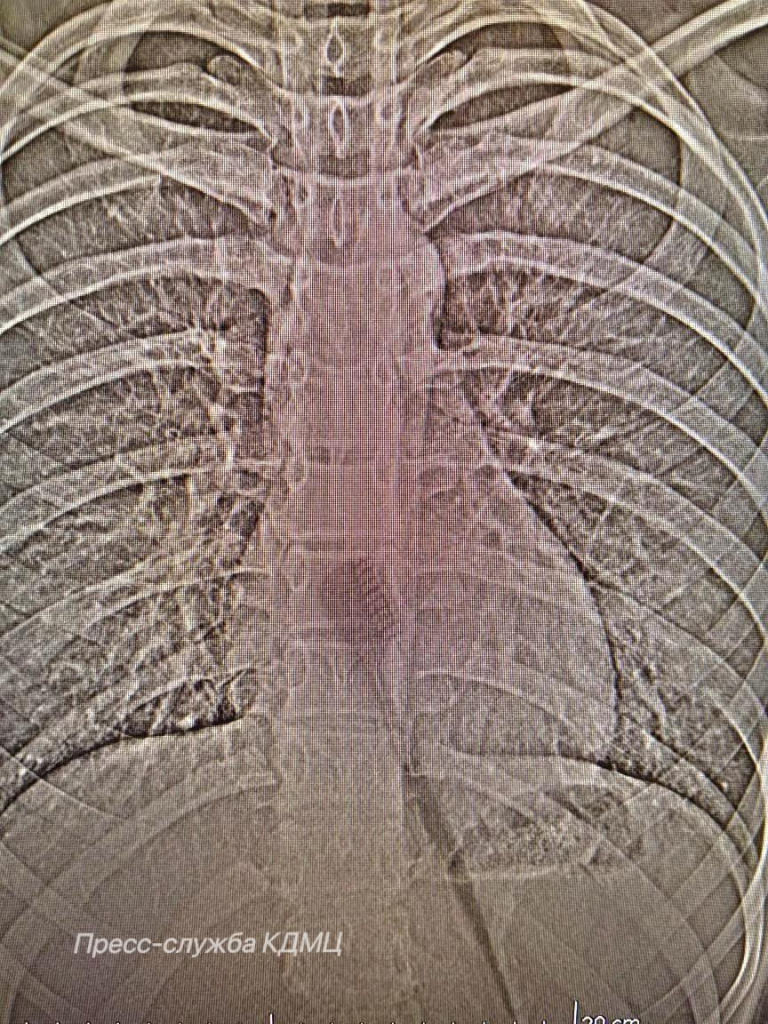

Как сообщили в пресс-службе Камского детского медцентра, в учреждении зафиксирован редкий случай: 13-летняя девочка проглотила зубную щётку длиной 19 см. во время утренней гигиены. Предмет застрял между желудком и пищеводом, рискуя травмировать оба органа. "Предположительно, произошла неожиданная реакция, возможно, резкий вдох или даже смех во время чистки зубов. Это могло спровоцировать непроизвольное сокращение мышц глотки, которое подтолкнуло щётку дальше по пищеводу. Так как анатомически пищевод имеет определённую эластичность, щётка, несмотря на свои размеры, смогла продвинуться вплоть до желудка", – пояснил врач-хирург КДМЦ Дамир Хузин. К счастью, операция не понадобилась – медики извлекли щётку через естественные пути с помощью эндоскопии. Девочка прошла реабилитацию и уже выписана.

Как сообщили в пресс-службе Камского детского медцентра, в учреждении зафиксирован редкий случай: 13-летняя девочка проглотила зубную щётку длиной 19 см. во время утренней гигиены. Предмет застрял между желудком и пищеводом, рискуя травмировать оба органа.

"Предположительно, произошла неожиданная реакция, возможно, резкий вдох или даже смех во время чистки зубов. Это могло спровоцировать непроизвольное сокращение мышц глотки, которое подтолкнуло щётку дальше по пищеводу. Так как анатомически пищевод имеет определённую эластичность, щётка, несмотря на свои размеры, смогла продвинуться вплоть до желудка", – пояснил врач-хирург КДМЦ Дамир Хузин.

К счастью, операция не понадобилась – медики извлекли щётку через естественные пути с помощью эндоскопии.